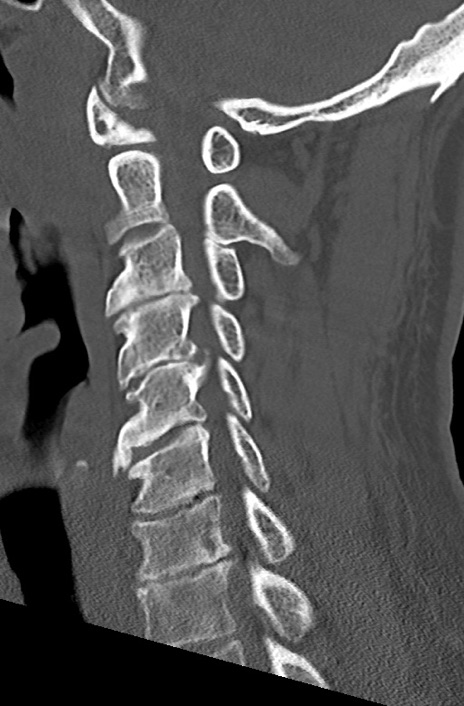

【整形】TIPS症例7 頚椎CT(矢状断像)

頚椎CT

矢状断像と横断像